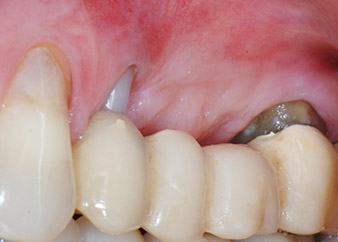

One month later, on the day of surgery, pain and inflammation at tooth 24 were minimal, but mobility of Miller class 2 was still present. After opening the flaps and cleaning the periapical and peri radicular infected tissue, the extent of the bone defect became obvious (Figs. 2 and 3).

At the buccal root, all vestibular and distal bone was missing. Attachment was essentially restricted to the palatal root, underlining the preliminary poor prognosis. Tooth 27 also showed a reduced horizontal attachment and a minimal apical rarefaction (cf. Fig. 1) without clinical symptoms.